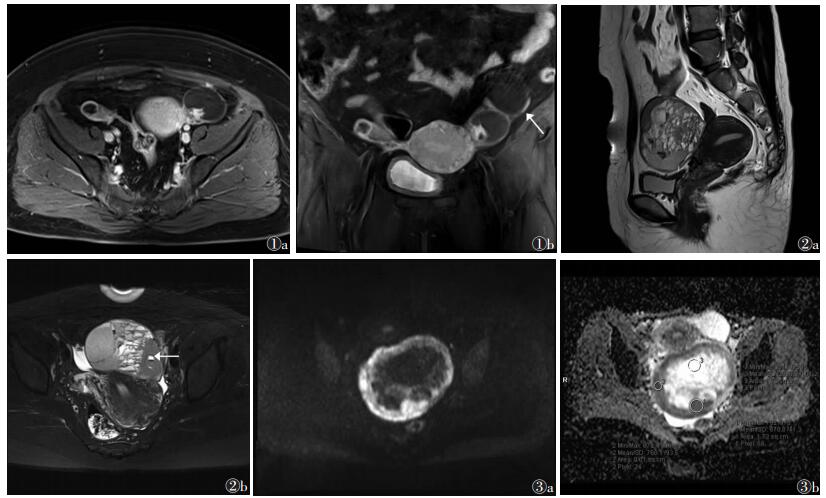

2.2 MRI表现12例中,左侧单发2例,右侧单发4例,肿瘤较大而无法明确其来源侧5例,双侧发病1例。其中1例为多房囊性,可见粗细不均的分隔,但无明确壁结节,发现时合并左侧盆壁异常强化结节及盆腔积液,考虑种植转移。1例为薄壁单一囊变型,肿瘤一侧见壁结节样实性成分突入腔内,实变结节内又可见小囊变,整体呈大囊小结节征(图 1a),同侧卵巢另见一系膜囊肿(图 1b)。1例为不均匀实质型,并为双侧发病,右侧卵巢肿物为OAGCT,左侧为成熟性畸胎瘤合并OAGCT,双侧病变信号混杂。9例为囊实性,但表现多样(图 2):1例肿物内见杂乱分布的簇状实变影及多发分隔样大小不等囊变区;1例病变中央呈坏死样囊变区,周围实变较多,但实性区域分布有分隔样线样强化,可能有继续囊变的趋势;2例呈蜂窝状,并可见大囊变区及分布无规律的片状实变区;2例囊变较多但无明确分隔;3例无特异性,呈实变区多发囊变。

| 图 1 女,47岁 图 1a,1b 分别为轴位和冠状位T1WI-fs增强扫描图像,示左侧附件区囊性肿块,可见壁结节,呈大囊小结节改变,小结节内见更小未强化液化区, 图 1b 示同侧附件区另一单纯囊性肿物,为系膜囊肿(箭头) 图 2 女,30岁 图 2a,2b 分别为矢状位T2WI和轴位T2WI-fs图像,示左侧附件区囊实性肿物,囊变较多,可见分隔,囊液信号多样化,囊变区出现小液平(出血可能)(箭头) 图 3 女,26岁 图 3a,3b 分别为轴位DWI和同层面轴位ADC图像,示盆腔巨大囊实性病变,实性部分(ROI1,ROI2)DWI呈明显高信号,ADC值较低,囊性部分(ROI3)DWI呈低信号,ADC呈高信号 |

与同层肌肉信号相比,肿瘤实性成分T1WI呈等或稍高信号,T2WI呈稍高或等信号;囊液呈T1WI低等或稍高信号,T2WI呈高信号。OGCT常合并瘤内出血,11例肿瘤囊变区可见数量不等的T1WI高信号灶,其中5例于囊腔内可见明确分层,下层为T2WI低信号细胞成分沉积;增强扫描实性部分呈中等至明显强化,囊性部分未见明显强化。

DWI及ADC值(图 3):肿瘤实性部分DWI(b=800 s/mm2)呈不同程度高信号,ADC值(0.116~1.214)×10-3 mm2/s,平均0.612×10-3 mm2/s;囊性部分DWI部分呈等或稍高信号,部分呈低信号,ADC值(0.306~2.851)×10-3 mm2/s,平均2.207×10-3 mm2/s。